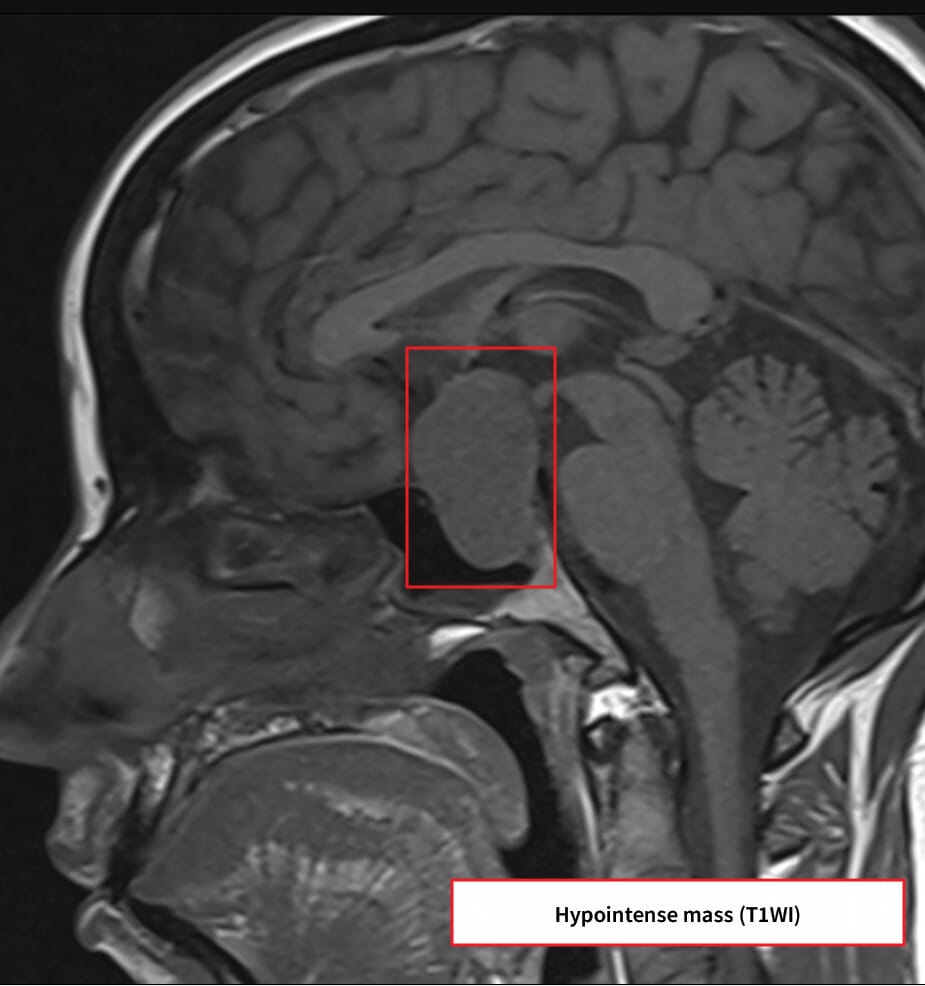

| 거대 선종(>10mm)에서 조영증강된 비균질 종괴로 나타나며, 주변 구조 압박 여부를 확인합니다. |

| ✅ 조영증강 MRI에서 불균질 조영 |

| 종양은 T1 조영에서 주변보다 낮은 조영도를 보이며 비균질한 양상입니다. |

| ✅ 시신경 교차 압박 가능성 |

| 상방으로 확장된 종양이 시신경을 눌러 시야장애를 유발합니다. |